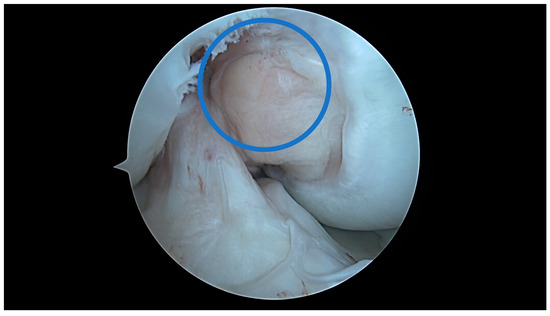

4.1. U-Shaped Notch

4.2. A/W Shaped Notch